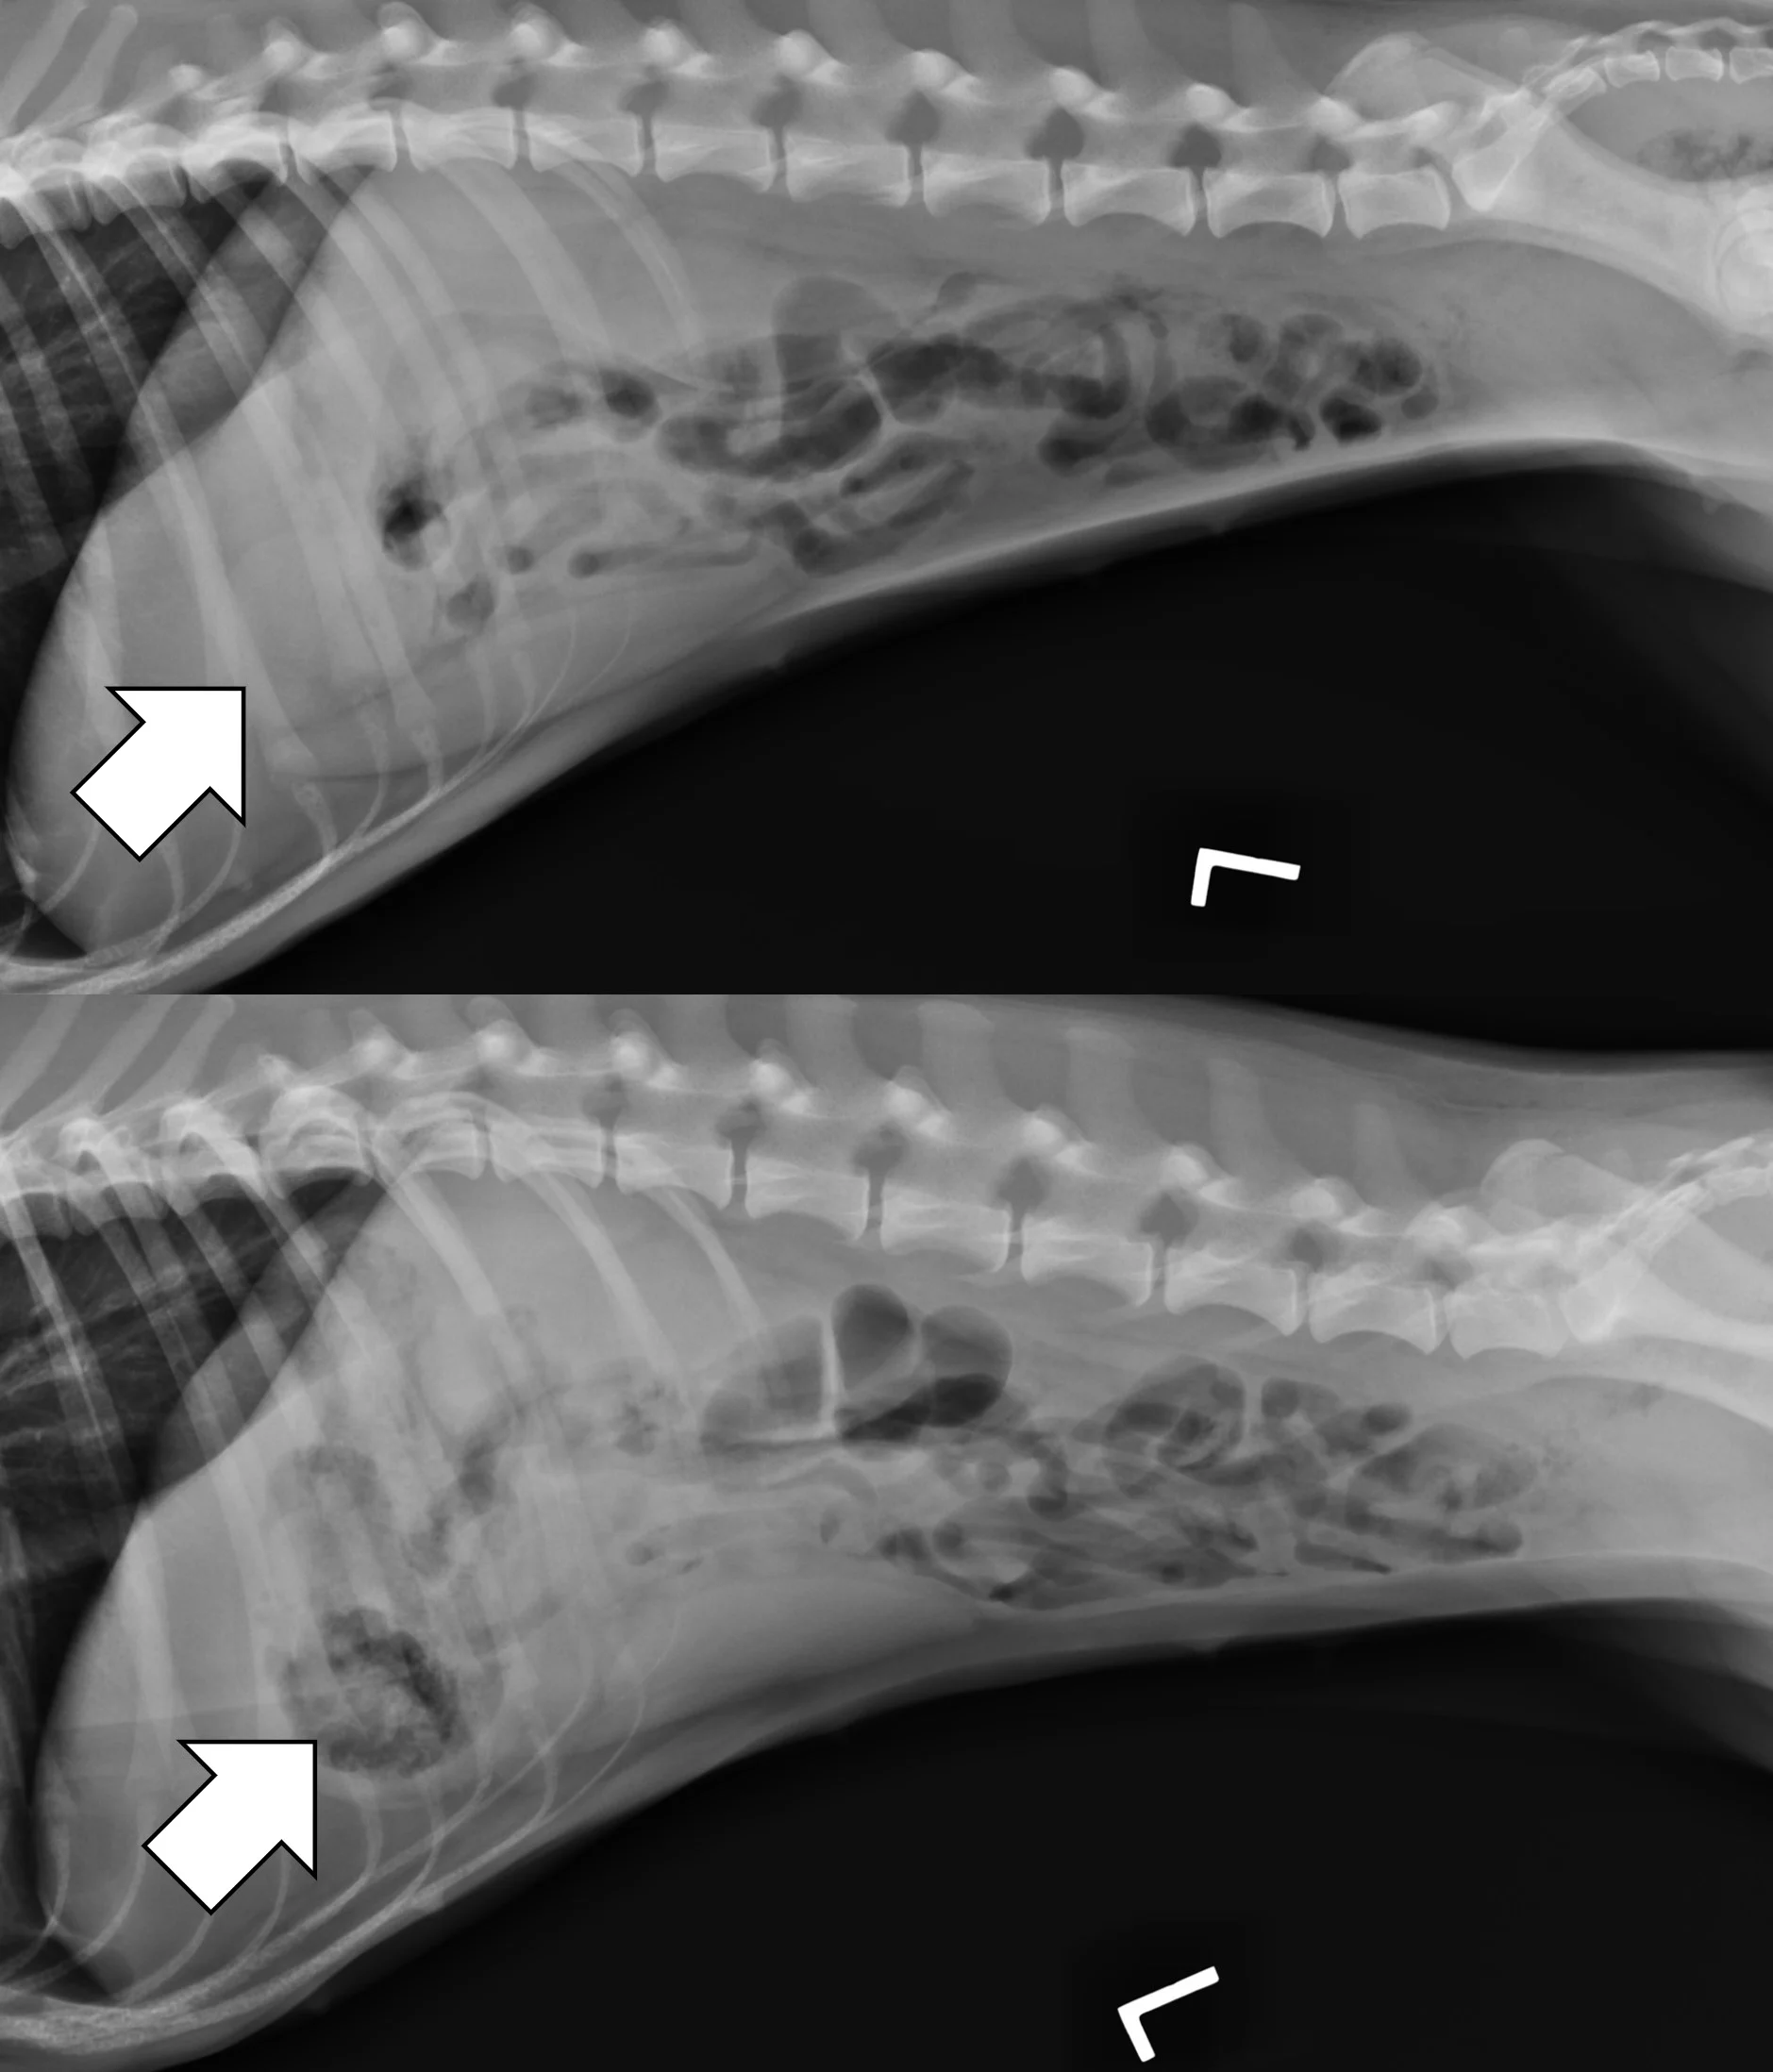

Linear foreign body obstructions occur when an object (eg, string, cloth) becomes stuck orally but extends aborally through the intestinal tract. Peristaltic contractions typically cause the small intestine to travel orally, eventually bunching. As a result, radiographic findings include intestinal bunching (ie, plication; Figures 5 and 6), an undulating serosal border, and angular or crescent-shaped gas bubbles. Obtaining a left lateral projection is critical because many linear foreign bodies anchor in the pylorus.

Right lateral radiographs of a 6-month-old spayed seal point crossbreed cat with a surgically confirmed acute linear foreign body (hair entangled in hair ties) obstruction. The small bowel is bunched in the midabdomen, making the plicated small bowel difficult to see (top, arrows). Normal small bowel displaces after compression with a wooden spoon, but the plicated bowel remains stationary and is easier to see (bottom, arrows).

In some patients, especially those that are obese, the small bowel loosely bunches, raising concern for a linear foreign body obstruction. Obtaining a lateral and/or ventrodorsal radiograph while gently compressing the region of concern with a wooden spoon can help differentiate physiologically bunched small intestine (easily disperses) from plicated bowel (does not disperse).